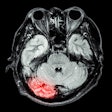

Cases of the Week

Check out our Cases of the Week!